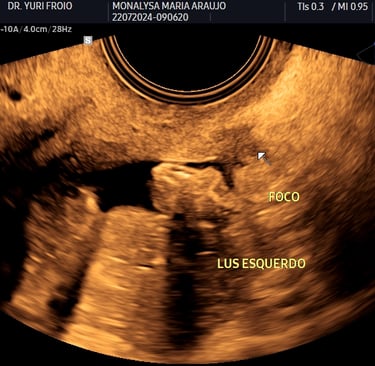

Foco de endometriose em ligamento ulterossacro esquerdo em paciente com queixas de cólicas e dores pélvicas.

4. Ultrassonografia para Diagnóstico de Endometriose

A endometriose é uma condição comum que pode causar dor pélvica e infertilidade. O ultrassom especializado, principalmente o transvaginal com preparo intestinal, pode detectar implantes endometrióticos profundos e orientar o tratamento.